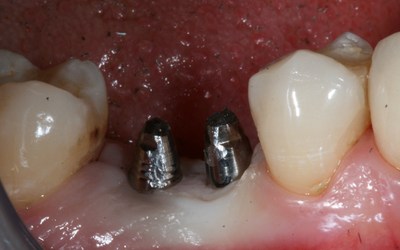

Абатмент при базальной имплантации

Происходит установка абатмента — соединительной части корня и протеза. Как правило, в однофазных имплантах часть корня и абатмент сделаны единой конструкцией, которая имеет 20-градусный угол наклона для параллельного правильного прикуса.